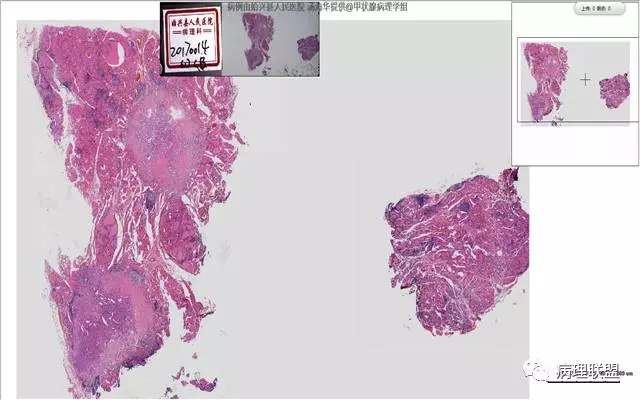

患者,女,45岁,发现双侧甲状腺肿物半月余。大体所见:左侧甲状腺肿物:4.3*5*4cm肿物一个,包膜完整,光滑,质脆,中央见出血。右侧甲状腺组织:3*1.6*1.5cm及1*1*0.8cm组织两块,其中较大的组织切开见内有0.8cm及1.2cm两个,质硬,灰白色,界不清,较小的,切开见灰黄色,质脆。